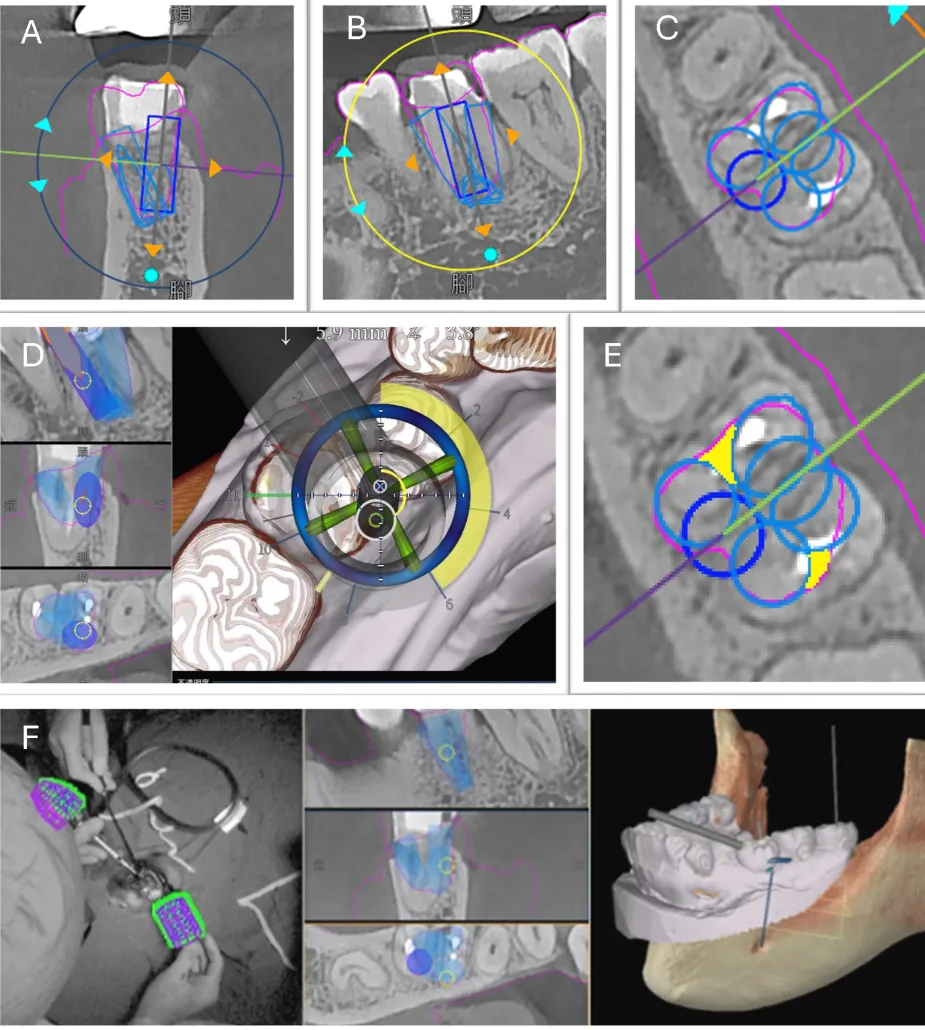

在人类尸体下颌骨研究中,针对基于 CAD-CAM 的数字化手术导板辅助自体牙移植技术进行了定位精度评估(图9)。结果显示,与自由手操作相比,导板辅助下的牙槽窝制备能更精确地匹配供体牙形态,大多移植牙在就位过程中仅需微调即可良好就位。这说明数字化引导技术在单根牙自体移植中具有较高的可行性和定位精度,展现出良好的临床应用前景。

图9(图引自Abella Sans F, Garcia-Font M, Nagendrababu V, et al. Accuracy of CAD-CAM Surgically Guided Tooth Autotransplantation Using Guided Templates and Custom-designed Osteotomes in Human Cadaver Mandibles. J Endod. 2023;49(8):1035-1043.

doi:10.1016/j.joen.2023.06.008)数字化手术导板辅助的自体牙移植:(A)拔除供体牙;(B)数字化手术导板辅助下受牙区牙槽窝预备;(C、D)确认受牙区牙槽窝预备情况;(E)3D打印供体牙模型试戴;(F)将供体牙移植到牙槽窝